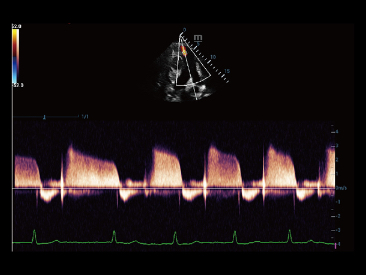

Fin dalla sua fondazione Mindray esplora continuamente nuovi modi per migliorare l'affidabilit├Ā diagnostica. Equipaggiata con la pi├╣ rivoluzionaria tecnologia ZONE Sonography?, la nuova piattaforma ZST+ di Resona 7 porta la qualit├Ā dell'immagine ecografica ad un livello superiore con l'acquisizione per zone e l'elaborazione dei dati canale.

Oltre alla qualit├Ā delle immagini di livello eccellente, Resona 7 migliora anche le capacit├Ā di ricerca clinica il rivoluzionario V Flow per la valutazione emodinamica vascolare, e l'acquisizione piani pi├╣ intelligente dal set di dati 3D per la diagnosi del sistema nervoso centrale fetale. Combinando il pi├╣ intuitivo funzionamento multi-touch basato su gesti e tutte le caratteristiche cliniche essenziali, Resona 7 sta veramente portando nuove tendenze nellŌĆÖinnovazione dellŌĆÖecografia.